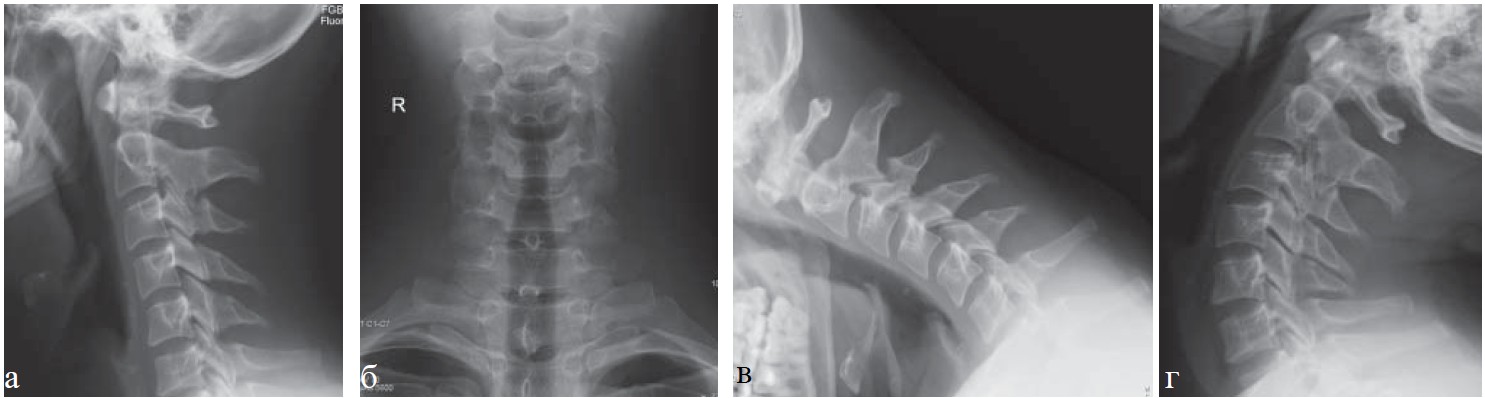

Рис. 2. Рентенография шейного отдела позвоночника, та же пациентка: а — прямая проекция; б — боковая, в — в положении максимального сгибания; г — в положении максимального разгибания. Определяются нарушение статики, начальные явления остеохондроза шейного отдела позвоночника (I степень).